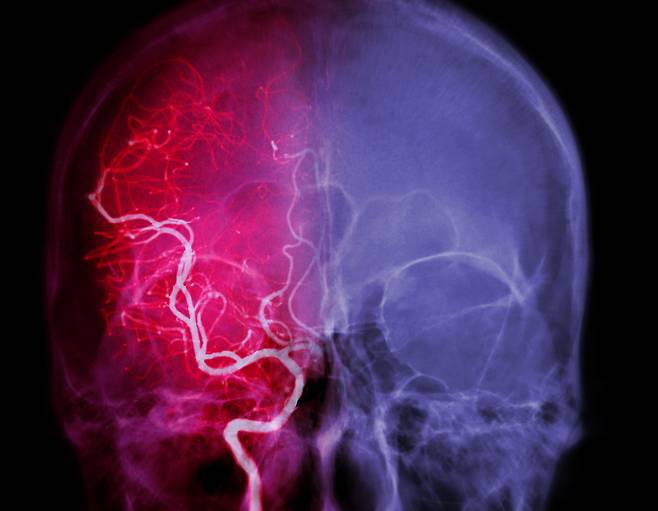

뇌 속 작은 혈관, 막히면 인지 저하… ‘이렇게’ 하면 증상 개선

뇌의 작은 혈관이 손상되거나 막히는 '뇌소혈관질환'을 앓고 있는 환자는 그렇지 않은 사람보다 '인지 기능'이 빠르게 저하한다는 연구 결과가 나왔다.

뇌의 대혈관이 막히거나 손상되면 뇌졸중, 뇌출혈 등처럼 증상이 명확히 나타난다. 하지만 뇌소혈관질환은 초기 단계 증상이 매우 미미하고 모호해 알아차리기 어렵다. 이대로 방치하면 뇌는 서서히 기능을 잃어간다. 주로 ▲손 떨림 ▲걸음걸이 느려짐 ▲언어 장애 ▲한쪽 입가나 손발 마비 등의 증상이 미세하게 보인다. 이땐 바로 병원을 찾아야 한다.

최근 고려대 의대 신철 교수팀이 뇌소혈관질환이 있는 중장년·노년층에서 인지 기능이 크게 감소한다는 연구를 '란셋 지역 건강-서태평양(The Lancet Regional Health-Western Pacific)' 저널에 게재했다. 연구팀은 49~79세 성인 2454명을 대상으로 뇌 자기공명영상(MRI)과 인지 능력을 추적해 8년 전과 후를 비교·분석했다. 2011~2022년 진행된 대규모 코호트 연구 데이터를 활용했다.

그 결과, 연구 참가자의 37%에서 뇌소혈관질환이 있었지만, 알지 못했다. 이들은 뇌소혈관질환이 없는 군보다 '집중력'과 '기억력'에서 뚜렷한 차이가 나타났다. 특히 시간이 지날수록 뇌소혈관질환이 있는 군의 인지 능력 저하가 가속화되는 것으로 나타났다. 신철 교수는 "중장년층과 노년층에서 뇌소혈관질환은 인지 기능 저하와 밀접하게 연관돼 있다"며 "특히 실행 기능인 집중력과 기억력에서 두드러진 차이가 나타났다"고 했다.